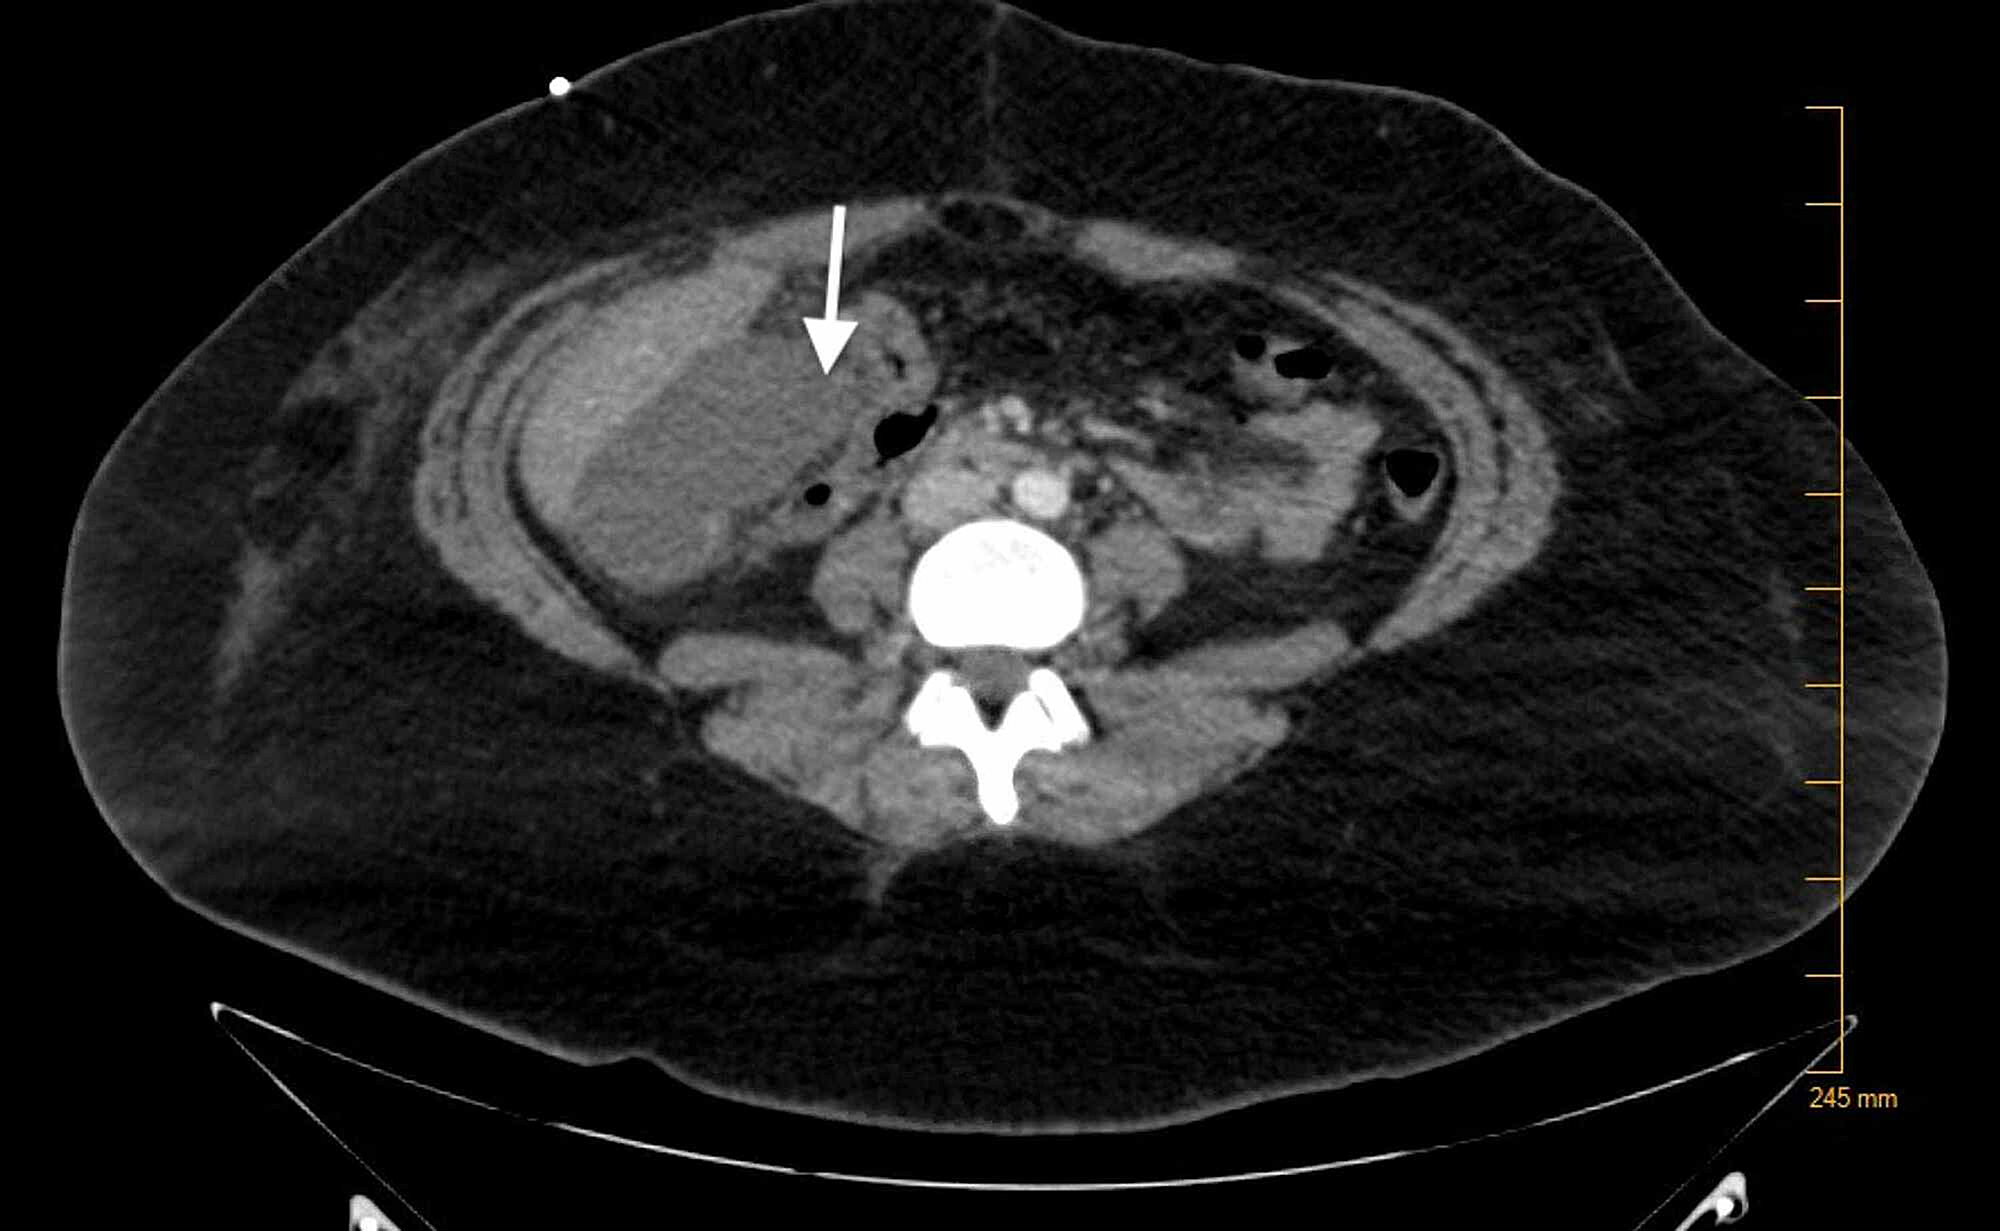

ct image shows collection of hypoattenuating fluid and air (arrow) in gallbladder fossa. collections of fluid in the gallbladder fossa can be detected by ultrasound in as many as 29% of patients following. endoscopic gallbladder drainage is a feasible and efficacious alternative to percutaneous drainage in the management of acute cholecystitis for. the role of imaging is to establish the diagnosis, delineate the extent of injury, and plan appropriate intervention. ct scan (a) shows surgicel (oxidized regenerated cellulose, johnson & johnson.

An axial CT image shows collection in the gall bladder fossa closely Fluid Collection Gallbladder Fossa ct scan (a) shows surgicel (oxidized regenerated cellulose, johnson & johnson. the role of imaging is to establish the diagnosis, delineate the extent of injury, and plan appropriate intervention. endoscopic gallbladder drainage is a feasible and efficacious alternative to percutaneous drainage in the management of acute cholecystitis for. collections of fluid in the gallbladder fossa can. Fluid Collection Gallbladder Fossa.